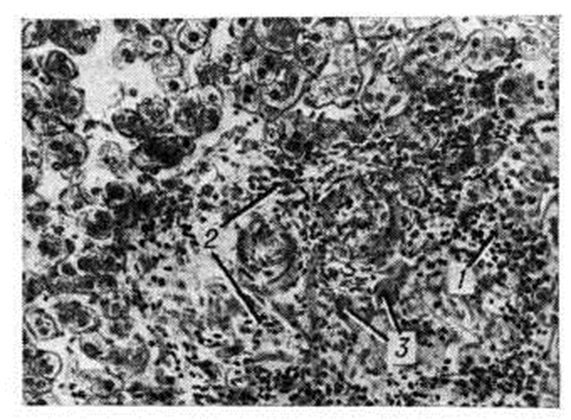

Хронический очаговые Гепатит (например., при бруцеллёзе, саркоидозе, туберкулёзе, альвеококкозе) имеют специфическую патологический картину, свойственную общей патоморфологии этих заболеваний (рисунок 1—4).

При поражении печени некоторыми грибками (актиномикоз), простейшими (амебиаз, балантидиаз) и гельминтами (аскаридоз, клонорхоз, фасциолез) наблюдаются гнойные Гепатит с множественными абсцессами. И. В. Давыдовский подчёркивал, что гранулематозный процесс более стереотипен, чем специфичен, так как обусловлен иммуногенезом и однообразием образующих гранулему клеточных элементов, которые при различных нозологических формах отличаются лишь своими сочетаниями.

Рис. 1. | ||